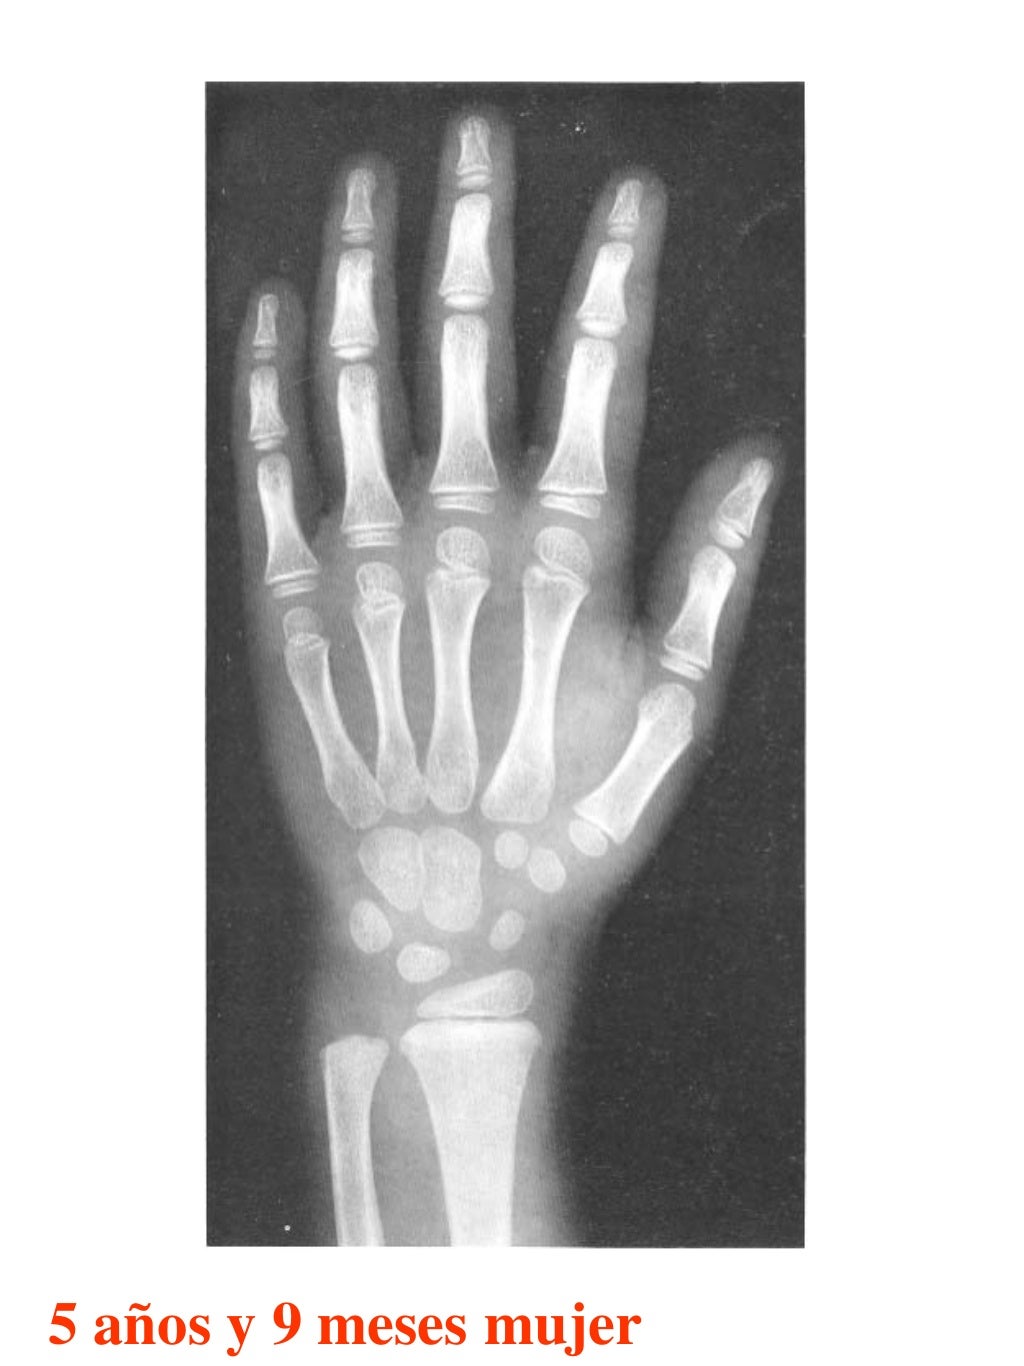

Tablas De Greulich Y Pyle The standards established by greulich and pyle, undoubtedly the most popular method, consist of two series of standard plates. The standards established by greulich and pyle, undoubtedly the most popular method, consist of two series of standard plates. El documento lista las edades. This systematic review summarizes the. The greulich and pyle method is one of the two main ways to assess the bone age of children. Both main methods of bone age. Scribd is the world's largest social reading and publishing site. 153 recomendaciones • 616,869 vistas. Atlas greulich y pyle | pdf | descarga gratuita. The greulich and pyle atlas is used to estimate the age of children and adolescents. The radiographic atlas of skeletal development of the hand and wrist by ww greulich and si pyle is a classic radiological.

Atlas greulich y pyle Tablas De Greulich Y Pyle The standards established by greulich and pyle, undoubtedly the most popular method, consist of two series of standard plates. Atlas greulich y pyle | pdf | descarga gratuita. Scribd is the world's largest social reading and publishing site. 153 recomendaciones • 616,869 vistas. The radiographic atlas of skeletal development of the hand and wrist by ww greulich and si pyle. Tablas De Greulich Y Pyle.